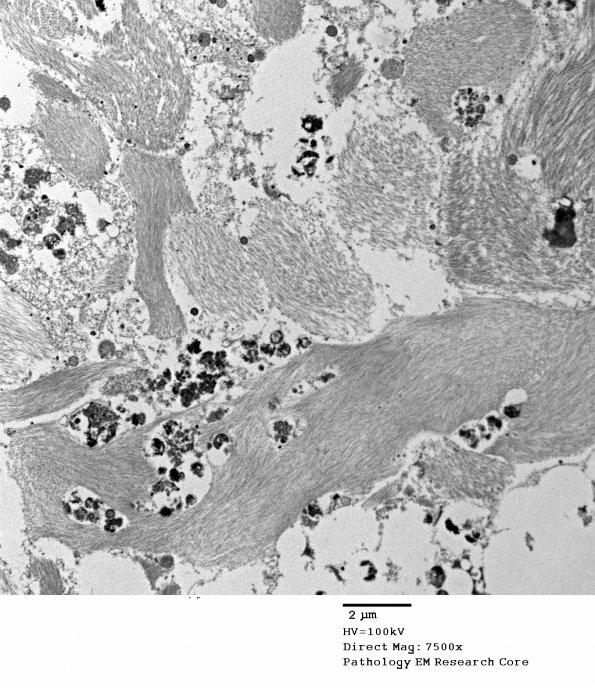

Ultrastructural examination was performed to better characterize the process. Note the large number of astrocytic processes with glial filaments, some of which have been labeled by hemosiderin, possibly externally (electron micrograph)